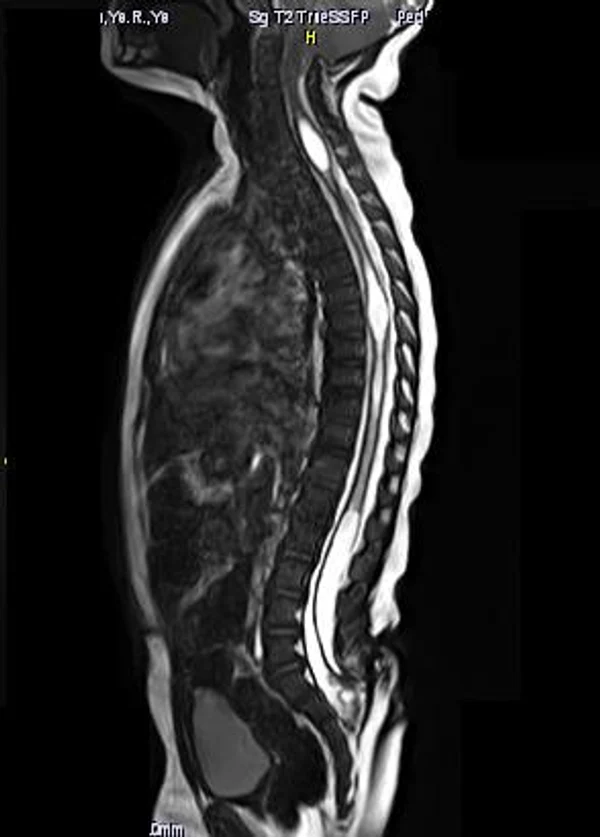

В своей практике с сирингомиелией мы сталкиваемся, как правило, в виде сочетанной аномалии у пациентов со спинальными дизрафизмами и/или аномалией Арнольда-Киари. Операции проводятся при увеличении размеров сирингомиелической полости в динамике, появлении или нарастании патологической неврологической симптоматики. При локализации сирингомиелии на шейном уровне, как правило, причиной ее развития является аномалия Арнольда-Киари. Хирургическое лечение заключается в проведении субокципитальной краниоэктомии, С1-2 ламинэктомии, устранение спаек в области большой цистерны, ревизии отверстия Мажанди и экспансивной дурапластики. После данной операции сирингомиелическая полость, как правило, регрессирует или уменьшается в размерах. Причиной сирингомиелии также может служить укороченная и утолщенная терминальная нить. В таких случаях первично выполняется рассечение терминальной нити. В остальных ситуациях при прогрессировании сирингомиелии на грудном или поясничном уровнях нами выполняется устранение фиксации спинного мозга на уровне сирингомиелии и сиринго-субарахноидальное шунтирование с помощью тонкого силиконового катетера (рис. 15).